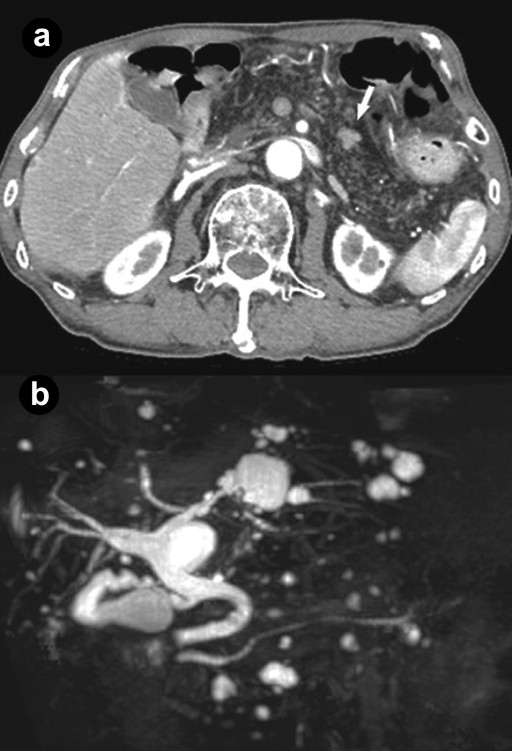

Figure 1. a. Abdominal dynamic computed tomography showed a slightly enhanced early phase 10 mm mass (arrow) in the pancreatic body, diffuse fat density, and net-like shadow in the entire pancreas. b. Magnetic resonance cholangiopancreatography demonstrated no abnormal findings, such as obstruction, narrowing or dilatation in the main pancreatic duct or multiple hepatic and pancreatic cysts. |

Lipomatous pseudohypertrophy was first described in 1931 [12] but it is a rare disease and the specific etiology of lipomatous pseudohypertrophy remains unknown. At CT imaging, this patient demonstrated typical features [13]. Histologically, the pancreatic acini showed marked atrophy and loss, but the islets of Langerhans were relatively preserved; hence, it was thought that glucose tolerance was preserved. In the residual scattered acini, low-grade PanINs, mucinous metaplasia, acinar atrophy, dilated ducts and slight lymphocytic infiltration were shown with a considerably high frequency. Altinel et al. reported that scattered acini do not show signs of injury, such as cellular attenuation, inspissated secretions or tubular complex formation [14]. However, it is unknown whether the above features of the acini in this patient occurred in association with diffuse fatty infiltrations or a minute pancreatic ductal adenocarcinoma because there have only been a handful of case reports about lipomatous pseudohypertrophy. In the literature, there are only three reports of pancreatic carcinomas associated with lipomatous pseudohypertrophy: one squamous cell carcinoma and two adenocarcinomas [14]. To date, 30 cases of lipomatous pseudohypertrophy have been reported [14], but the study of carcinogenesis in lipomatous pseudohypertrophy patients has been extremely limited. In this patient, two risk factors, advanced age and smoking, might be involved in the possible occurrence of pancreatic cancer. Until now, it has been unclear whether lipomatous pseudohypertrophy should be considered as a risk factor for pancreatic ductal adenocarcinoma. However, if lipomatous pseudohypertrophy of the pancreas is observed, careful attention should be paid to the risk of carcinogenesis.